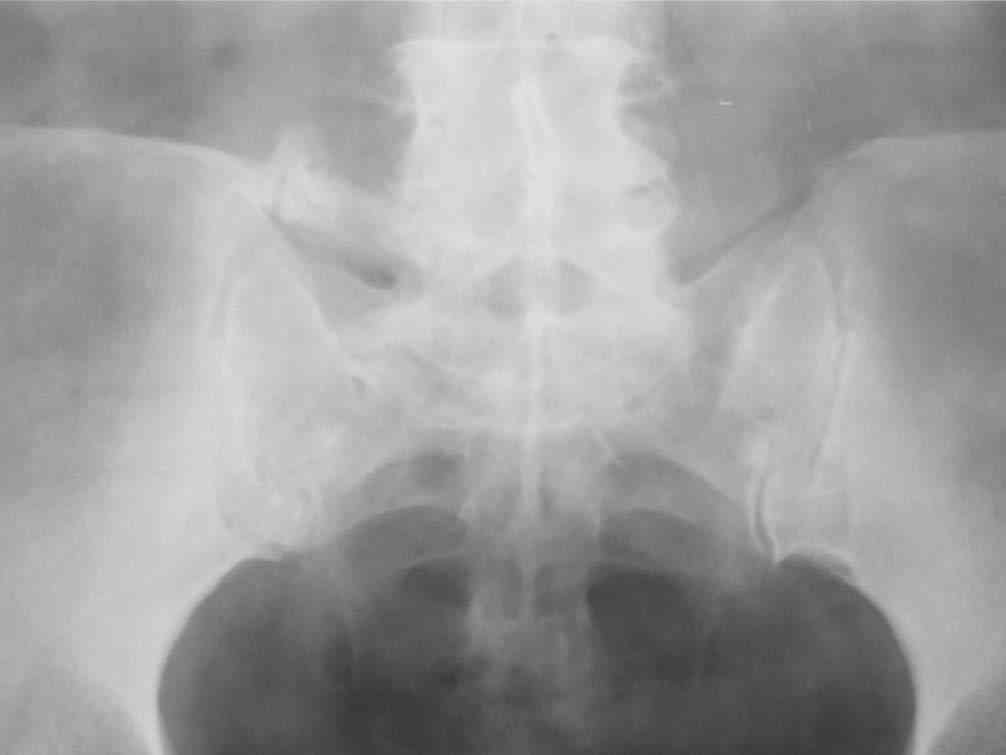

Уважаемый Юрий Алексеевич! Спасибо огромное за подробное письмо, Ваш опыт бесценен, обязательно воспользуюсь. Отправляю рентгенограмму пациентки.